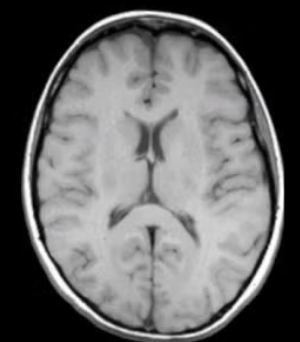

T1 weighted

Which type of CT contrast highlights fat and anatomy: fat is bright; water is dark?